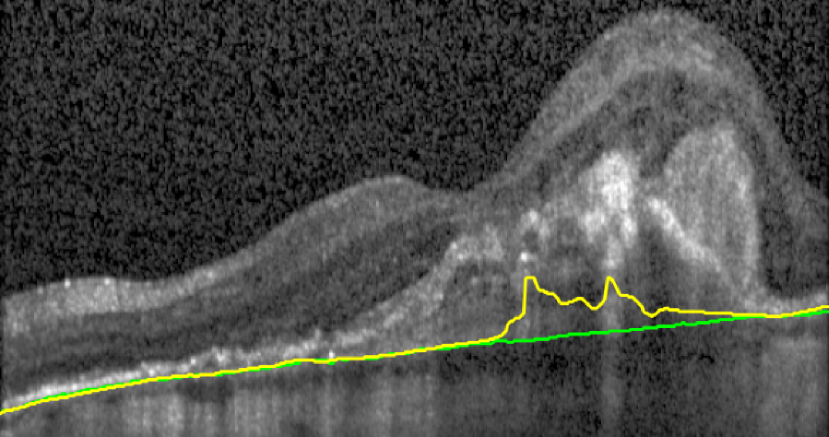

Bruch’s Membrane is an elastic smooth and thin structure, strategically located between the retina and the general circulation, having a crucial role in retinal function, aging and disease [14]. Automated segmentation of the BM is particularly important in the context of AMD as, unlike other common retinal diseases such as DR, RVO, or glaucoma, the BM is distinguishable from the outer RPE boundary. In specific, drusen in iAMD and PEDs in nAMD separate the RPE from BM, requiring the segmentation of the region in-between them. In addition, in case of GA, the RPE is completely lost in some locations, exposing only the BM, thus imposing additional difficulties for algorithms and calculations that depend on the RPE position. Achieving correct automated identification of the BM is challenging in many cases, mainly due to the small thickness of this layer, the high reflectivity of the RPE that shadows parts of the BM, and the noise being present in the scans, which is often indistinguishable from the content of drusen and PEDs (Fig. 4). Due to these difficulties, currently many automated solutions either do not provide a segmentation of the BM or its segmentation is often inaccurate in retinal OCT with AMD, leaving this clinically relevant segmentation task unaddressed or under-explored.

(a) iAMD

(b) nAMD

(c) GA